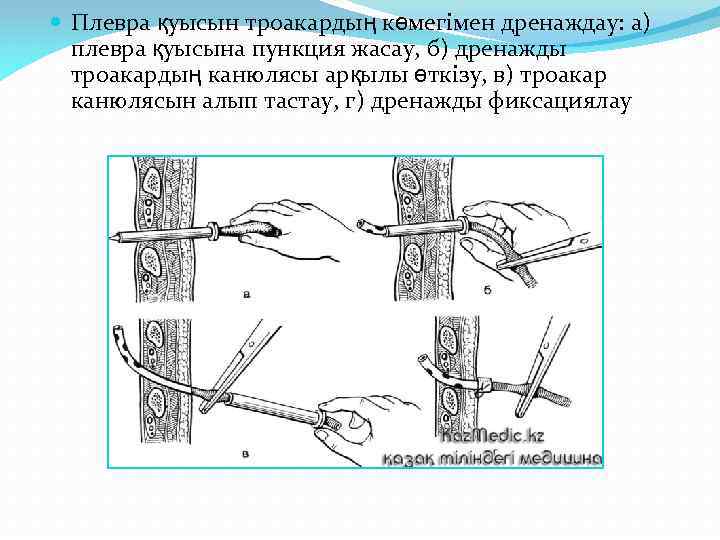

Плевра қуысын троакардың көмегімен дренаждау: а) плевра қуысына пункция жасау, б) дренажды троакардың канюлясы арқылы өткізу, в) троакар канюлясын алып тастау, г) дренажды фиксациялау